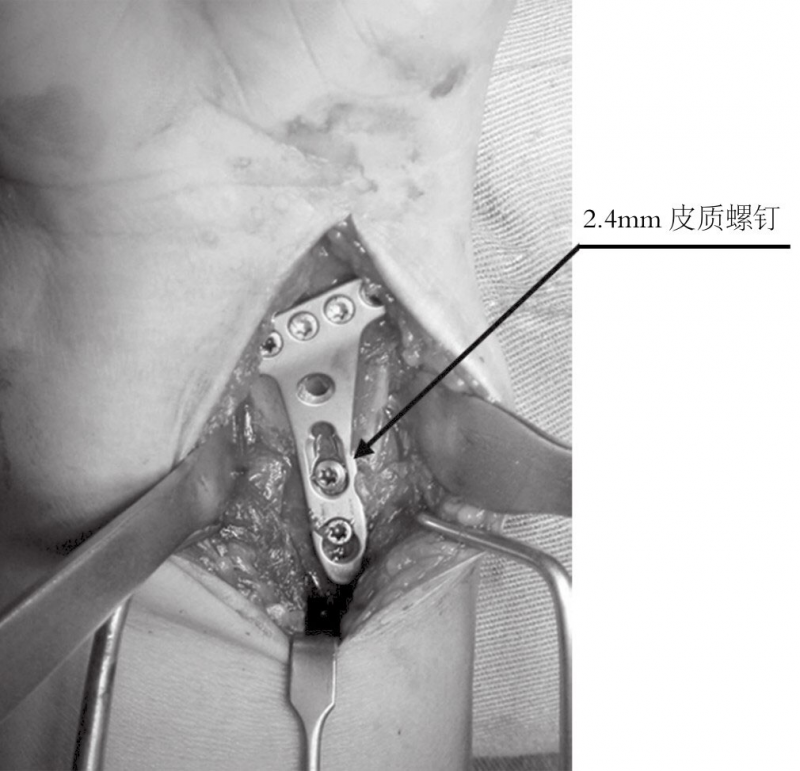

远端的锁定螺钉首先置入。接着用一枚普通的2.4mm皮质螺钉置入,将钢板贴向桡骨远端骨面。

由于有远端固定角度的锁定螺钉,钢板紧贴桡骨干能够增加桡骨远端关节面的倾斜度,所以要选用最靠近桡骨干的螺钉孔置入头侧锁定螺钉(图5)。

图5 最后复位和骨折的固定